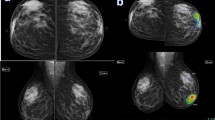

In the current work, an AI abnormality scoring, and the category was given to each breast; 13/50 (25%) breast lesions were deemed malignant (Fig. 3), and 38/50 (74.5%) breast lesions were deemed benign.

A fifty-five-year-old lady presented with a mass in the right breast. Mammography showed right upper outer quadrant focal asymmetry with a cluster of microcalcifications seen within as shown in a. The US revealed right breast atv0 o'clock altered parenchyma mounting to mass formation. AI software revealed right breast upper outer quadrant showed an overlaid heat map, high lighting the area of suspicion with PoM scoring 99% indicating a malignant lesion as shown in b. The final diagnosis was right breast DCIS